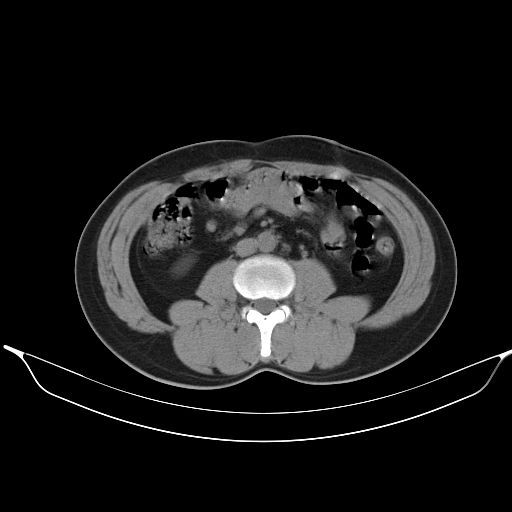

2、轻度脂肪肝。

转移性肺肿瘤不排除,建议结合相关检查考虑

1、均为转移,原发灶不在肺内。2、肺癌肺转移。